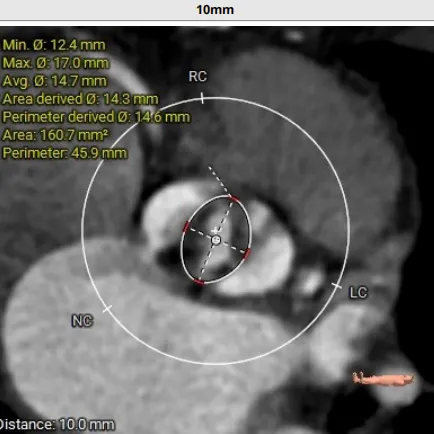

术前CT评估:TYPE 0型二叶瓣,瓣叶肥厚,前后交界粘连,瓣叶无明显钙化,双冠异窦,左冠开口高度约16.6mm,右冠开口高度约16.7mm。法式窦结构小,STJ高度约21.6mm,直径约24.4mm,升主动脉未见明显增宽,心脏角度约42°,左室大小尚可,心尖部可见局部心肌薄弱。

TYPE 0型二叶瓣,瓣叶肥厚,前后交界粘连,瓣叶无明显钙化

钙化积分:0mm³,无钙化